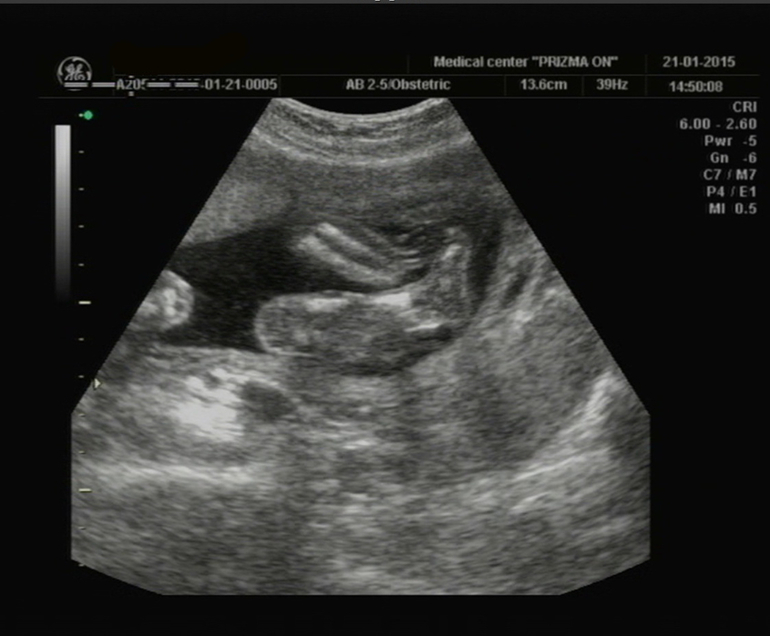

Наши ножки

кулачёк